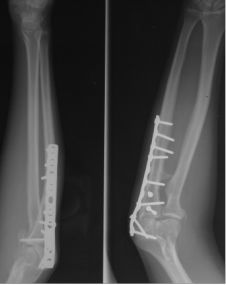

补救比较好

补救:取下一枚钉子骨折愈合了,关键是取钉子后减少了应力集中,延长了钢板的寿命,骨折愈合了。如果骨不愈合钢板迟早断裂(钢板当初放在内侧会好,蝶形骨块不会坏死,腓骨固定后外侧稳定,内外柱均衡愈合机会增加,当然最好还是髓内钉)。

取下3枚钉子骨折愈合了,与上一例同一位医生所做。张力带钢板,去除3螺钉后,钢板的应力分散,弹性增加,骨折端承受有效的应力刺激,最后骨折愈合。去除螺钉的时候如果加骨皮质剥离重新激发骨愈合会更好。(最好选髓内钉)